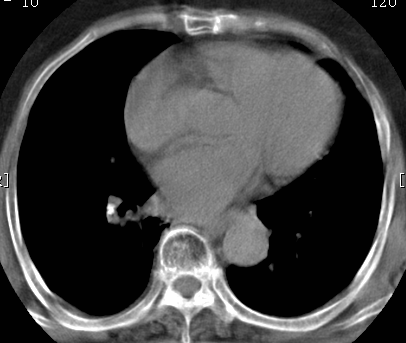

标题: CT26680:肺部右下肺静脉干结节的界定 [打印本页]

标题: CT26680:肺部右下肺静脉干结节的界定

经追查说有支扩咯血病史,但不确定

考虑1、周围型肺癌,2肺静脉畸形,前者可能大,建议增强检查。

考虑1、周围型肺癌,2肺静脉畸形,前者可能大,建议增强检查。支持!

不排除右肺下叶周围型肺癌可能。

中心型肺癌,纤支镜可帮助明确。